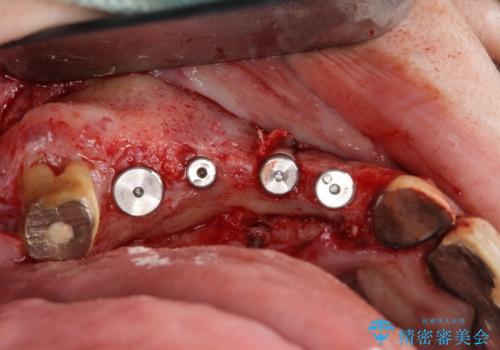

既に埋入されているインプラントは位置が悪いのでそのまま骨内に留置することとし、新たに咬合機能を回復すべく3本のインプラントを埋入すると同時に吸収した骨幅を増やし、安定してインプラントで噛める環境整備を目指します。

- 120万円(インプラント×3 チタンカスタムアバットメント×3 メタルボンドクラウン×3 骨造成 歯肉移植)費用は治療当時の料金となります

インプラントが長持ちするために、インプラント周囲の十分な骨量・角化歯肉の存在・安定した咬合を一つづつ整備する治療を行いました。